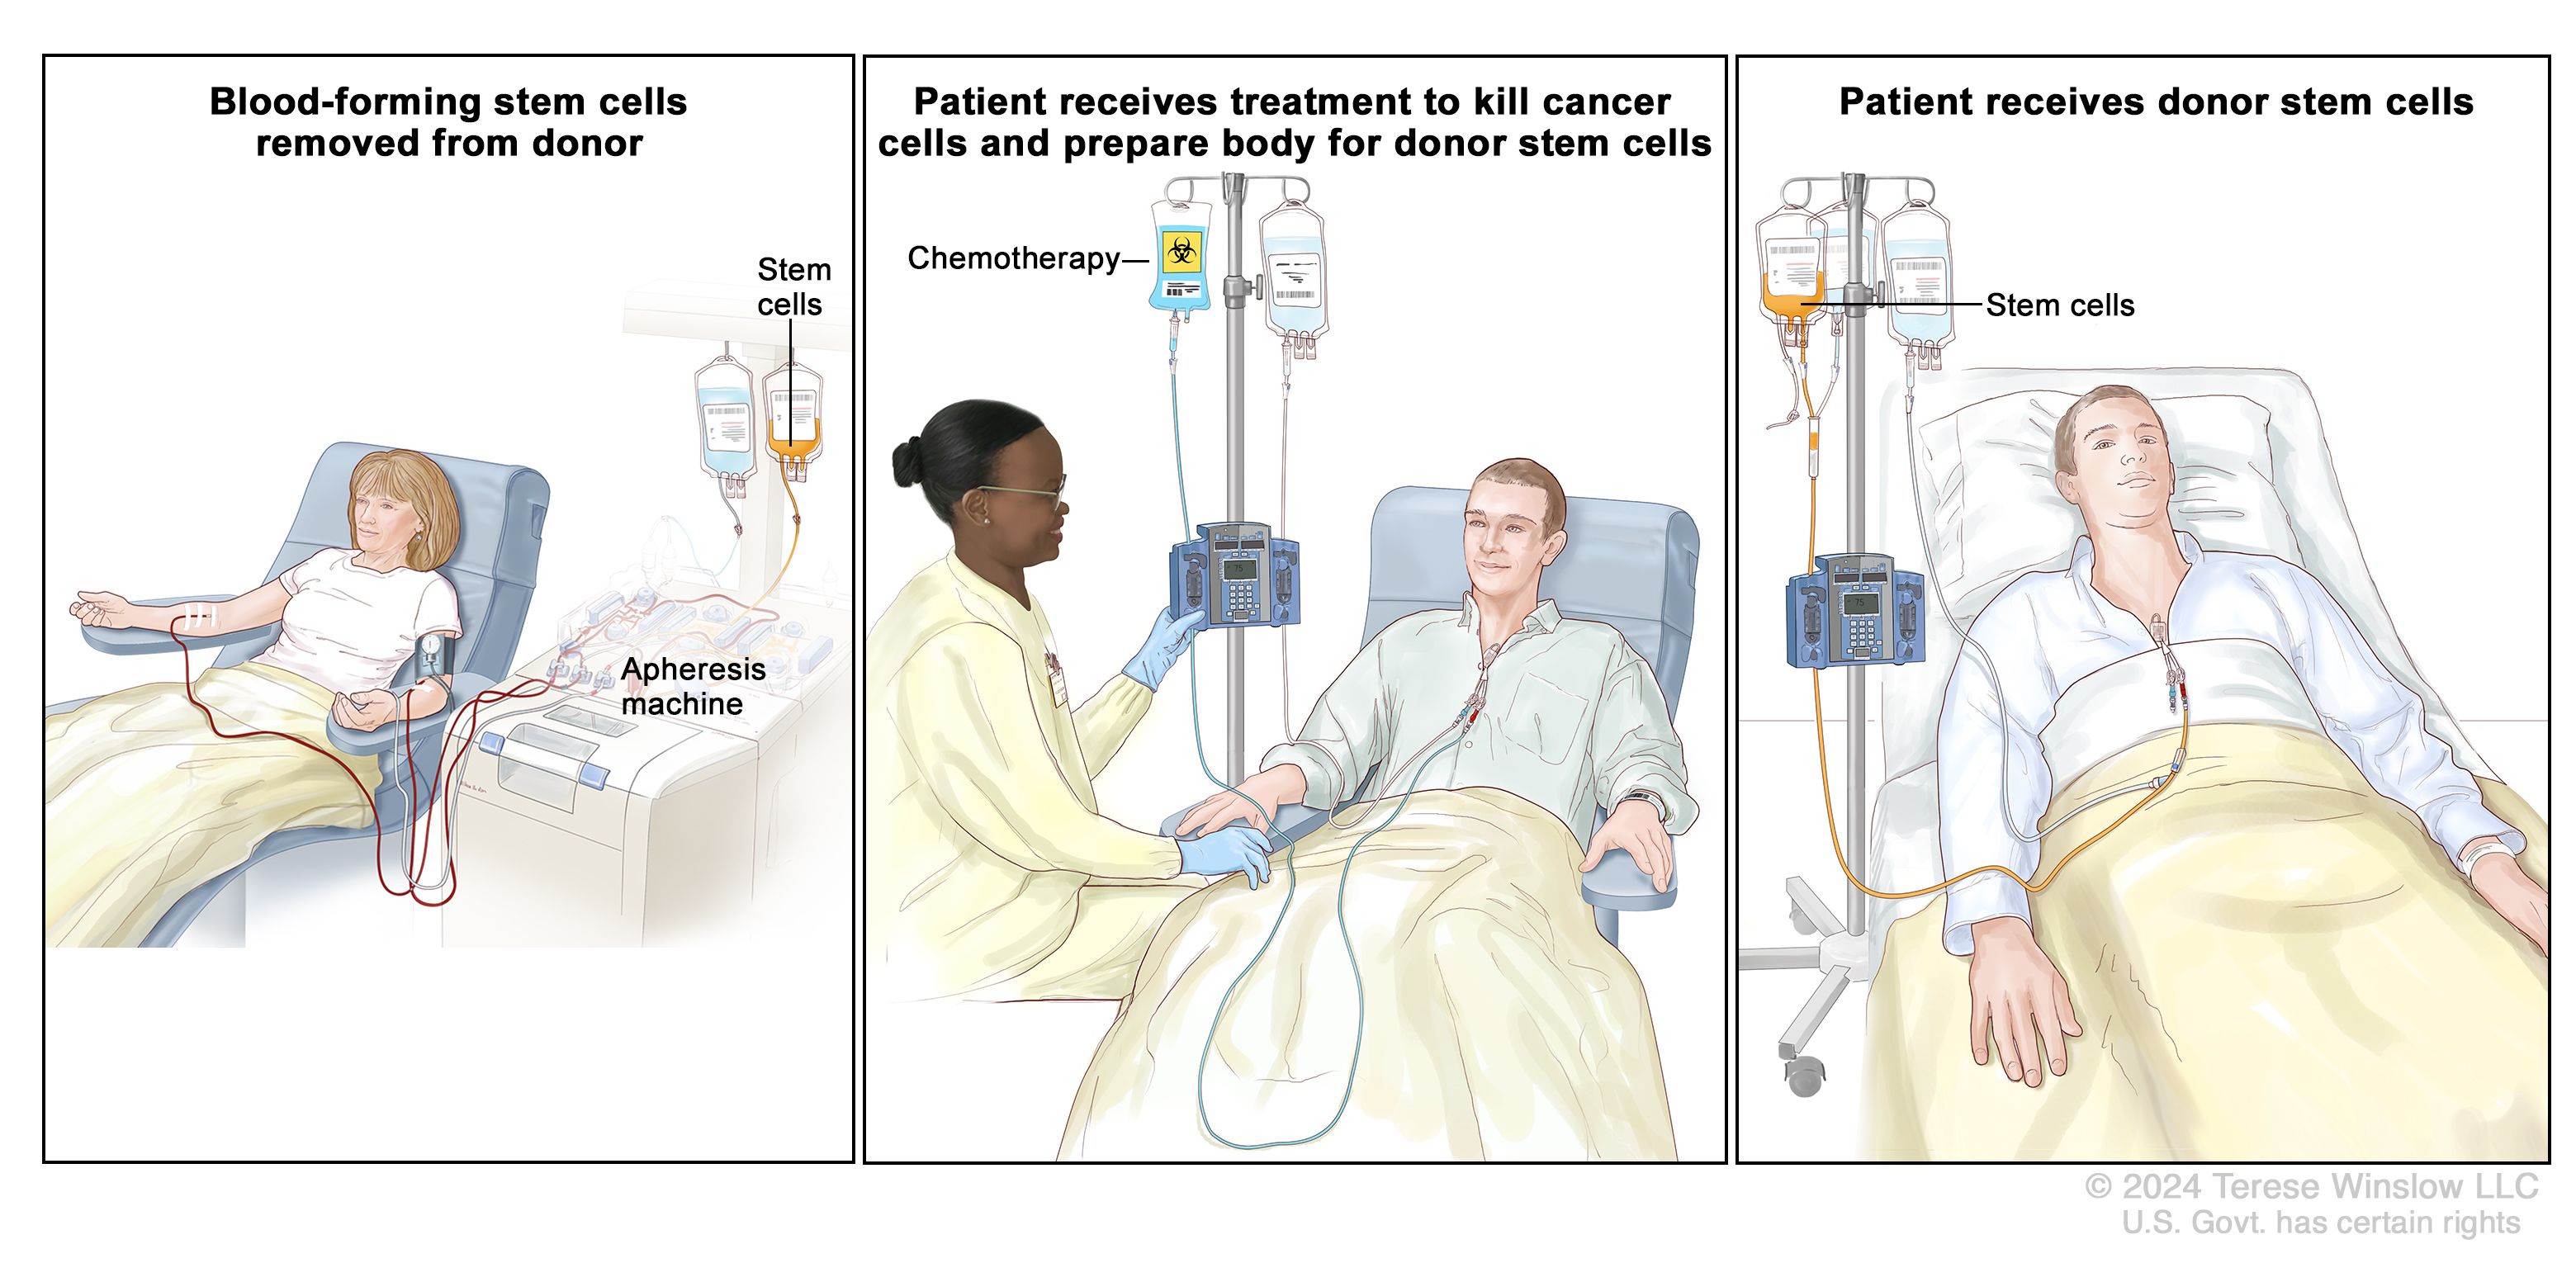

Read MoreOncology Surgery

Oncology Surgery is a specialized branch of medicine focused on the surgical …